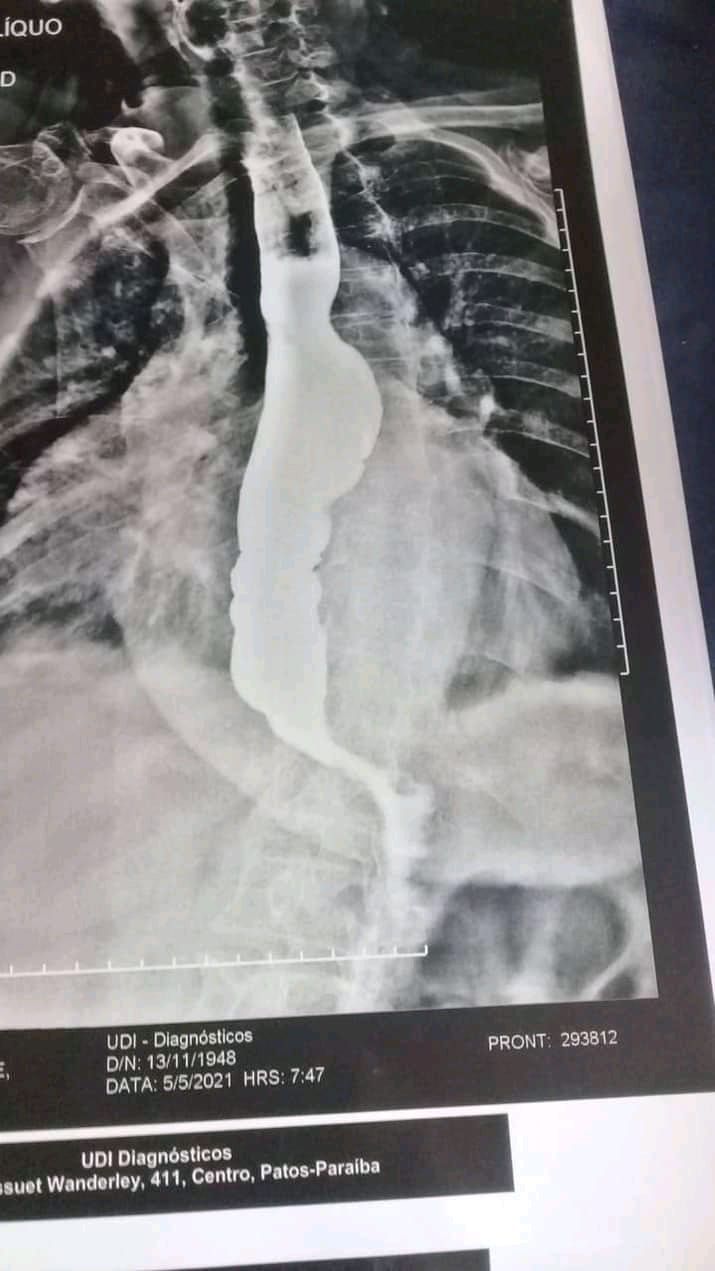

De acordo com Ednaldo Zabumbeiro, filho de Dona Maria, o procedimento chamado mega de esôfago custa mais R$ 3.500,00 em cada diária no Hospital Samaritano da capital, e não foi conseguido por meio do SUS, após procurar a Secretaria de Saúde de Patos.